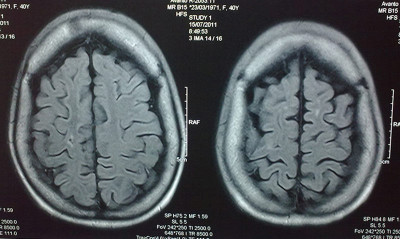

Casos Neuroloquirúrgicos

Envíado por Dr. Ruben Eduardo Amaya Contreras